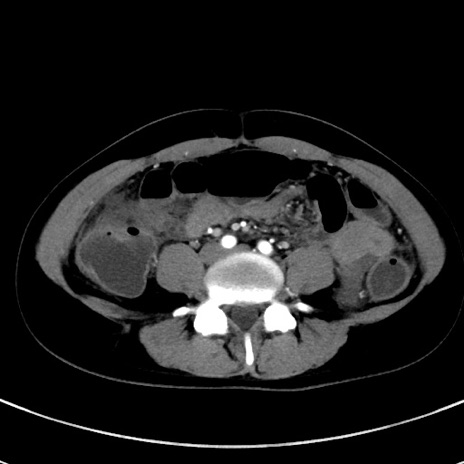

症例17(横断像)

【症例】20歳代女性

【主訴】嘔吐、下腹部痛

【現病歴】昨日夕食後に嘔吐し下腹部痛が出現。本日になっても嘔吐持続し改善しないため来院。

【身体所見】意識清明、BT 37.2℃、BP 108/67mmHg、腹部:平坦、やや硬、下腹部正中から右にかけて圧痛あり、反跳痛軽度あり、tapping pain(+)。

【データ】WBC 13600、CRP 14.94